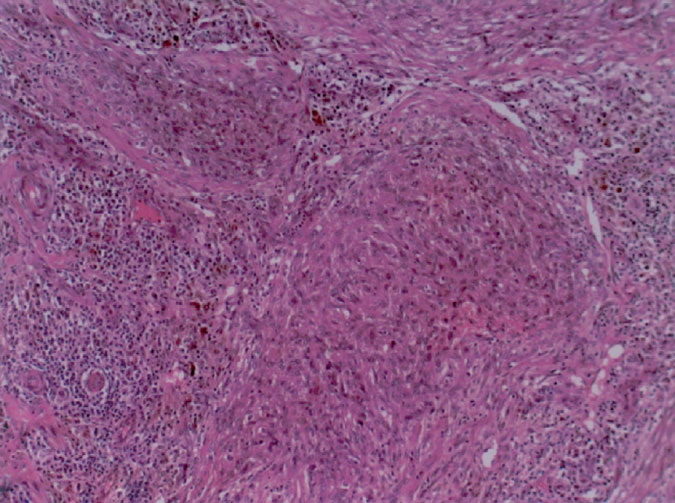

Angiomatoid fibrous histiocytoma =ورم الناسجات الليفي الوعاؤمي